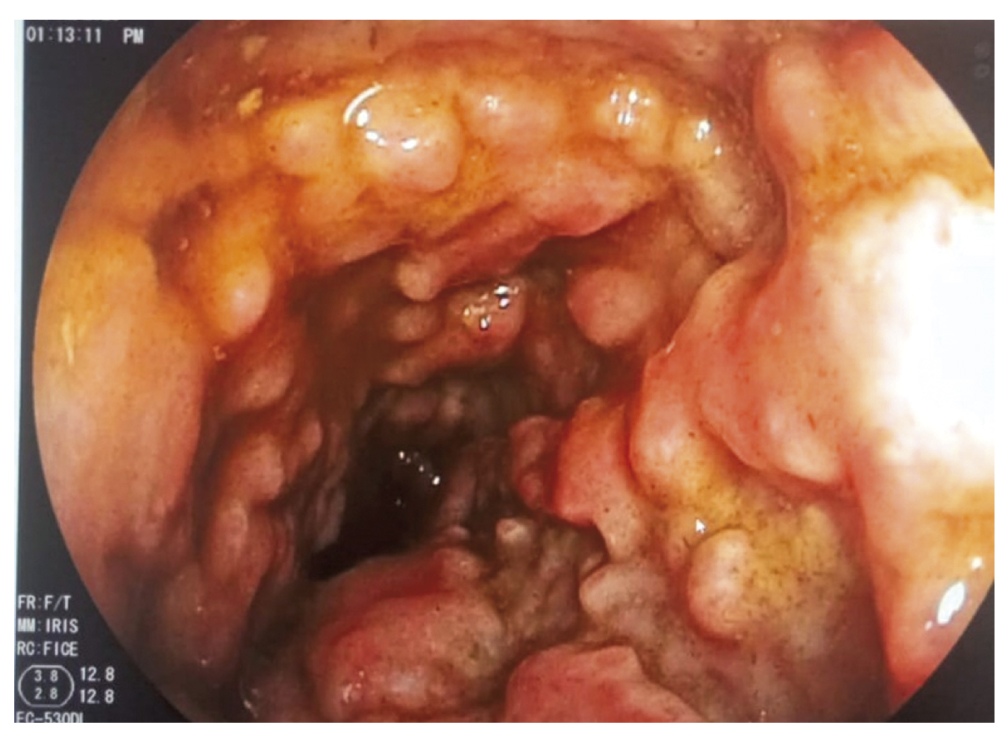

19.03.2023 — Учитывая диарейный синдром, системную воспалительную реакцию и антибактериальную терапию в анамнезе, с целью оценки степени поражения толстой кишки и диагностики псевдомембранозного колита пациенту была проведена колоноскопия с осмотром до нисходящей ободочной кишки. Начиная с прямой кишки, с тенденцией к увеличению количества и размеров, визуализировались множественные бляшковидные очаги желтоватого цвета, размером от 3 мм до 15 мм; вокруг бляшек была отмечена гиперемия и усиление сосудистого рисунка.

Заключение: эндоскопическая картина псевдомембранозного колита (рис. 1).

Рис. 1. Множественные бляшковидные очаги желтоватого цвета на слизистой оболочке в прямой кишке.

Fig. 1. Multiple plaques in the rectum.